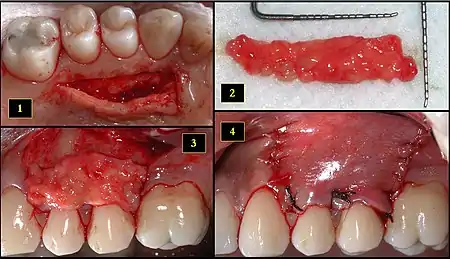

Subepithelial connective tissue graft

- Recipient site exhibits gingival recession on both premolars and first molar (molar recession is not an esthetic issue and will not be treated)

- Incisions prior to flap reflection

- Full thickness flap elevated

- Another viewpoint of the flapped recipient site